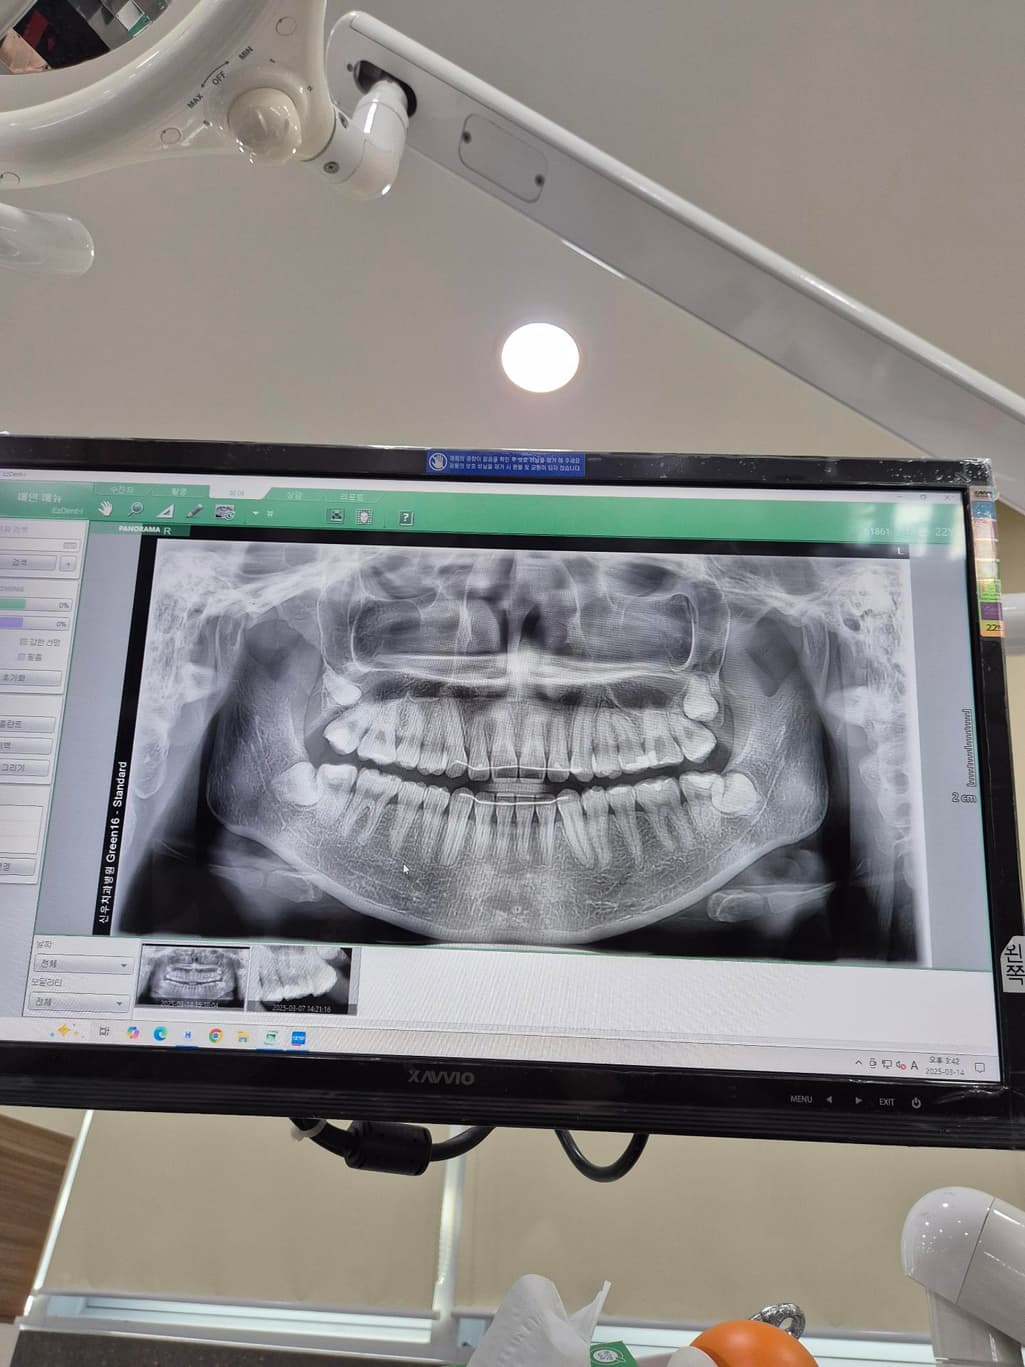

x레이 사진은 5개월 전 사진입니다. 나중에 치아가 흔들리까봐 걱정됩니다.

사진으로 봤을 경우에는 잇몸 퇴축이 조금 진행된 것으로 보입니다. 잇몸 대축은 잇몸에 너무 강한 자극이 가해지면서 생기기 때문에 양치질을 할 때 잇몸에 넘어가는 자극이 가해지지 않다고 하는 것이 좋습니다.

나이 대비하여 잇몸이 조금 퇴축된 것은 맞습니다. 지금부터 관리를 더 잘해주셔야겠습니다.

송곳니는 원래 잇몸퇴축이 다른 치아보다 먼저, 더 많이 이뤄집니다 교정 후 잇몸퇴축이 동반되는 것은 흔한 부작용 중 하나이고요 앞으로 잇몸관리 꾸준히 치과에서 받으세요